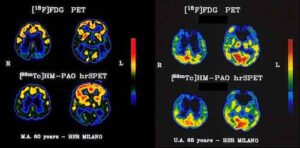

Alzheimer in età giovanile: sottovalutati i sintomi